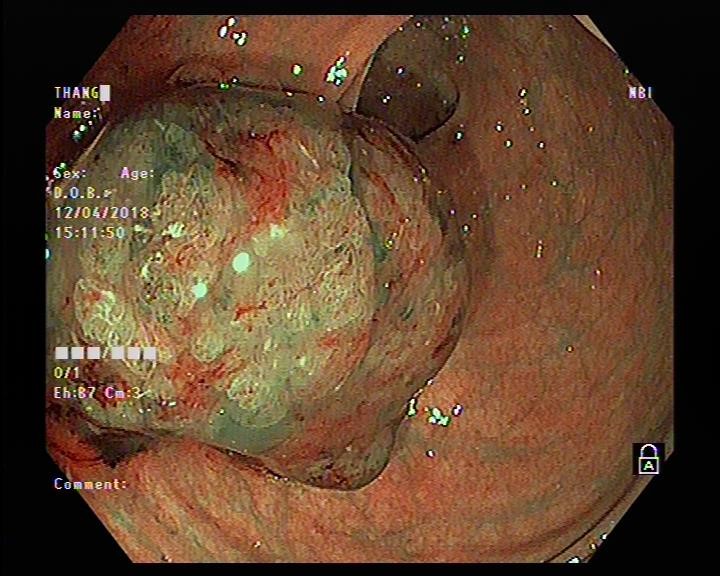

NỘI SOI TIÊU HÓA KHÔNG ĐAU TẦM SOÁT UNG THƯ SỚM TẠI BVDK TỈNH HẢI DƯƠNG

12/06/2024 (GMT+7)

Nội soi tiêu hóa là phương pháp nội soi chẩn đoán hình ảnh các cơ quan tiêu hóa như thực quản, dạ dày, tá tràng, đại tràng hay trực tràng. Đây là một trong những phương pháp chẩn đoán điều trị hiện đại nhất hiện nay, giúp phát hiện sớm nhiều bệnh lý tiêu hóa trong đó có ung thư nguy hiểm.